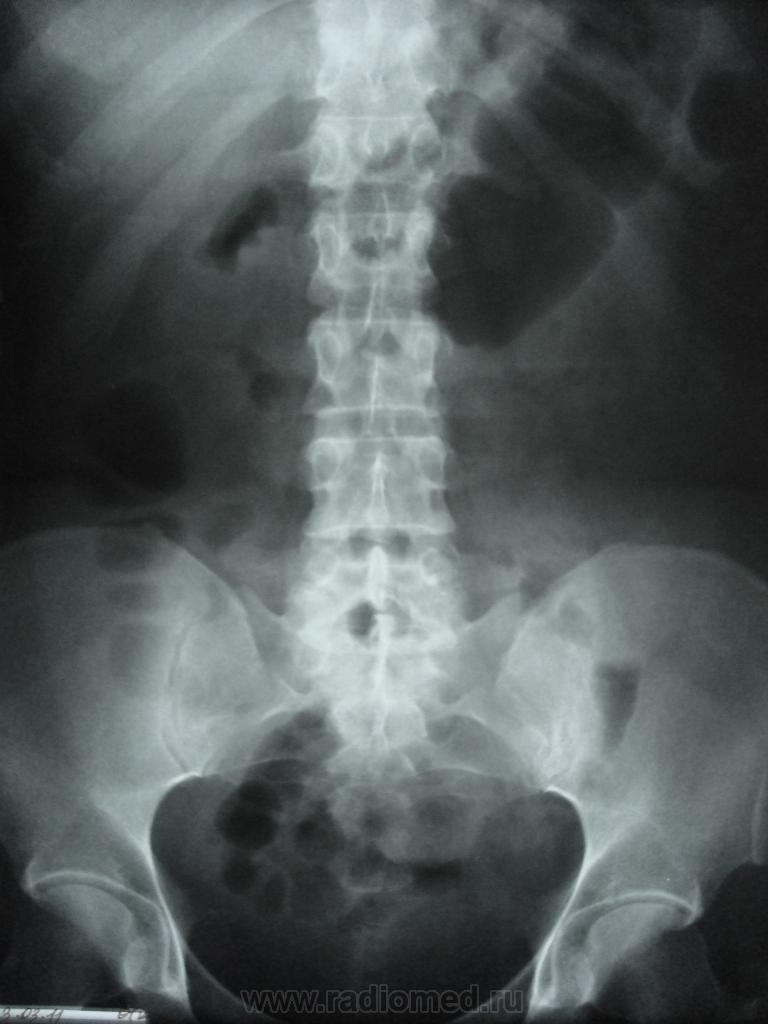

Добрый вечер уважаемые колллеги! пациент-женщина, клиника-почечная колика справа. По УЗИ расширение ЧЛС справа. у меня возник небольшой спор с урологом, говорит что причина расширения ЧЛС справа не конкремент, а так называемое ими РЛС, или добавочные сосуды мочеточника, за неимением практики не стала с ним спорить, но и писать в заключение это не стала. Что это и с чем это едят?))))))))))))) (сказал не путать добавочные сосуды почек с добавочными сосудами мочеточника)

Спорить с клиницистами не стоит. Как правило, они тупее рентгенологов, кругозор их уже, а цели сиюминутны. Тем не менее, именно они - Исцелители и Избавители. Смиримся с этим и будем исполнять СВОЮ работу: Описание + Заключение. Что мы видим на данной серии? Несомненное нарушение уродинамики справа с препятствием на уровне терминального отдела мочеточника. Конкремент ли это? Визуально это не доказано, поэтому в заключении звучать не может. Уролог может связать клинику с анализом мочи и ренгензаключением, и поставить диагноз "Мочекаменная болезнь", а рентгенолог нет. На будущее: если, после последнего снимка, пациента отправить помочиться, и сделать снимок после опопрожнения, то мелкий конкремент в устье мочеточника можно было бы визуализировать. П.С. Ваш уролог тот еще фантазер: предполагаемые им ///добавочные сосуды мочеточника/// тоже надо визуализировать, а это возможно только при КТ, а без этого, его рассуждения - суть пустейшая фраза.

Камень не камень, но признаки затруднённого оттока на уровне устья правого мочеточника очевидны.Отсюда вторичные изменения в ЧЛС и мочеточнике..

камень был в в/3 правого мочеточника....Всем спасибо)))))))))))))